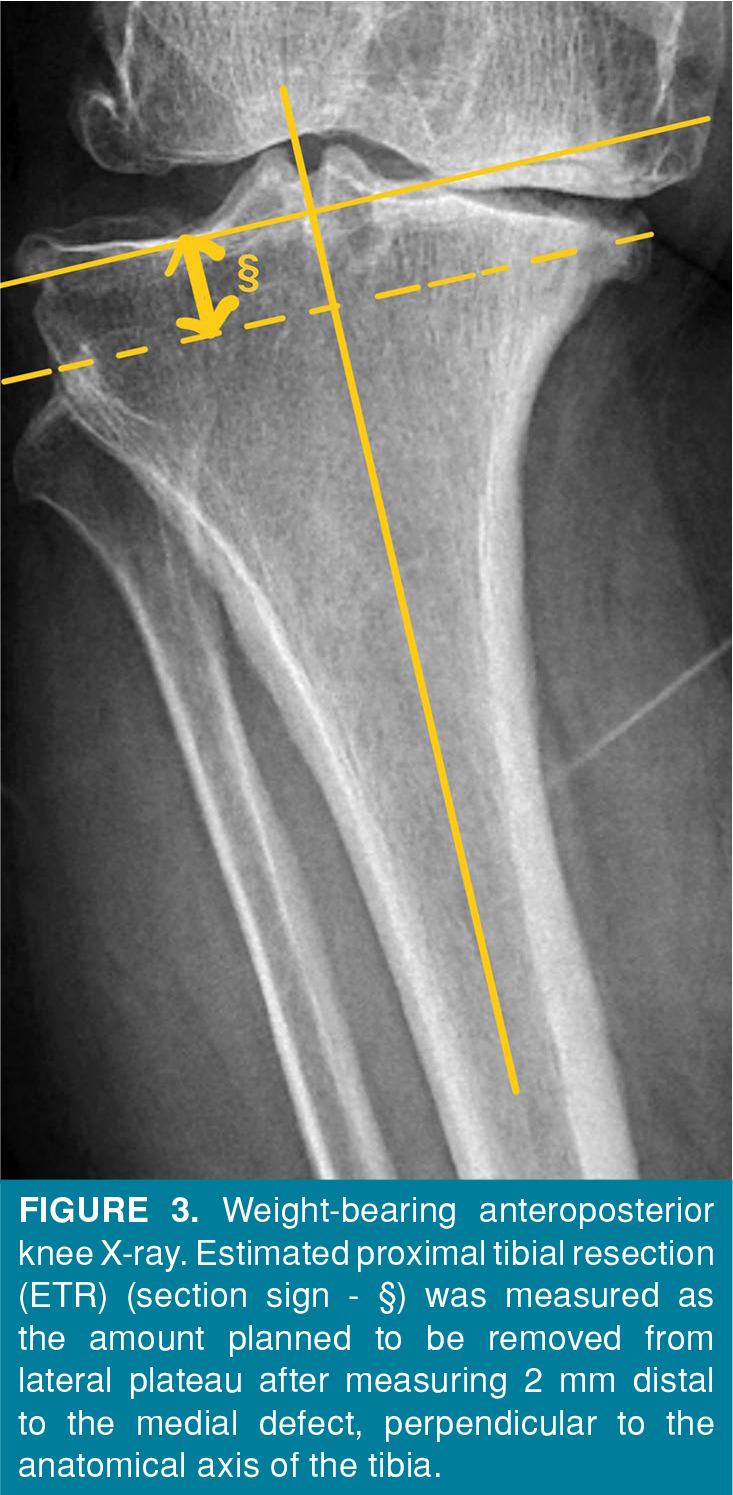

Patients and methods: Between October 2022 and April 2024, a total of 87 knees (51 right and 36 left) of 82 patients (11 males, 71 females; mean age: 68.7±8 years; range, 53 to 86 years) who underwent primary TKA were retrospectively analyzed. The patients were divided into two groups as patients who underwent primary TKA with and without tibial metal augmentation. There were 39 patients and 42 knees in the group with metal augmentation and 43 patients and 45 knees in the group without metal augmentation. The HKA angles and amount of preoperative planned tibial resection (ETR) were evaluated. Cut-off values for preoperative HKA angle and ETR were determined using receiver operating characteristic (ROC) analysis.

Results: The mean pre- and postoperative HKA angles were 18.98±4.42° and 6.58±3.48°, respectively and the mean ETR was 13.91±3.02 mm. Both groups were comparable in terms of postoperative HKA angles p=0.283). The mean preoperative HKA and ETR were significantly higher in TKAs with augmentation (p<0.001 for both). The probability of needing augmentation was approximately six times higher in knees with a preoperative HKA angle of >20.6° (OR=5.909, 95% CI: 2.065-16.91, p<0.001) or ETR of >12.52 mm (OR=5.816, 95% CI: 2.202-15.359, p<0.001).

Conclusion: In TKA with advanced varus deformity, tibial metal augment is a method that can be used to provide soft tissue balance. The need for metal augmentation should be kept in mind, particularly if the preoperative evaluation indicates that the HKA angle exceeds 20.6° or ETR exceeds 12.5 mm.